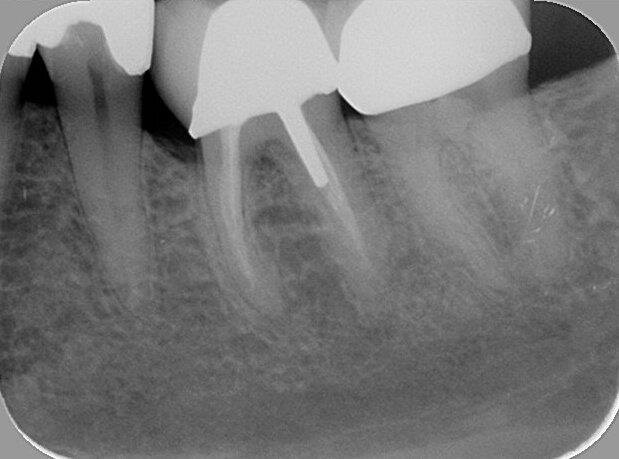

Een 23-jarige vrouw meldde zich bij mij in de praktijk met een pijnklacht aan de 36. Het element was sinds een paar dagen pijnlijk met koud, en intra-oraal onderzoek kon de klachten van de patiënt reproduceren. Röntgenologisch was een diepe amalgaamrestauratie met een para-pulpaire pin zichtbaar (afb. 1). De diagnose luidde een irreversibele pulpitis, en na het toedienen van lokale anesthesie werd het element onder rubberdam gebracht en werd een endo ingezet.

Afb. 1: Bitewing van het tweede en derde kwadrant